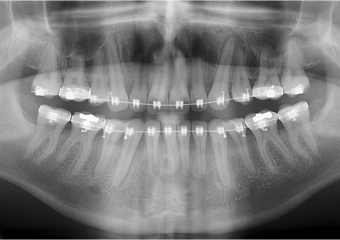

Raio x inicial